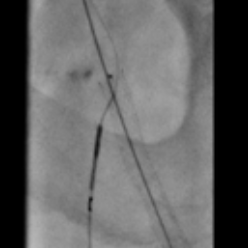

• Unique needle design / shape, axial protrusion or lateral protrusion selector, with excellent pushability and torqueability

• Highly stable support from a very low profile 4Fr catheter with a 0.018" catheter guidewire and 2.9Fr catheter with a 0.014" catheter guidewire

• Unique RO marker directly on the needle provides both radial and axial needle position information

• Unique catheter with the ability to advance laterally Inside hard plaque with its needle fully or partially deployed